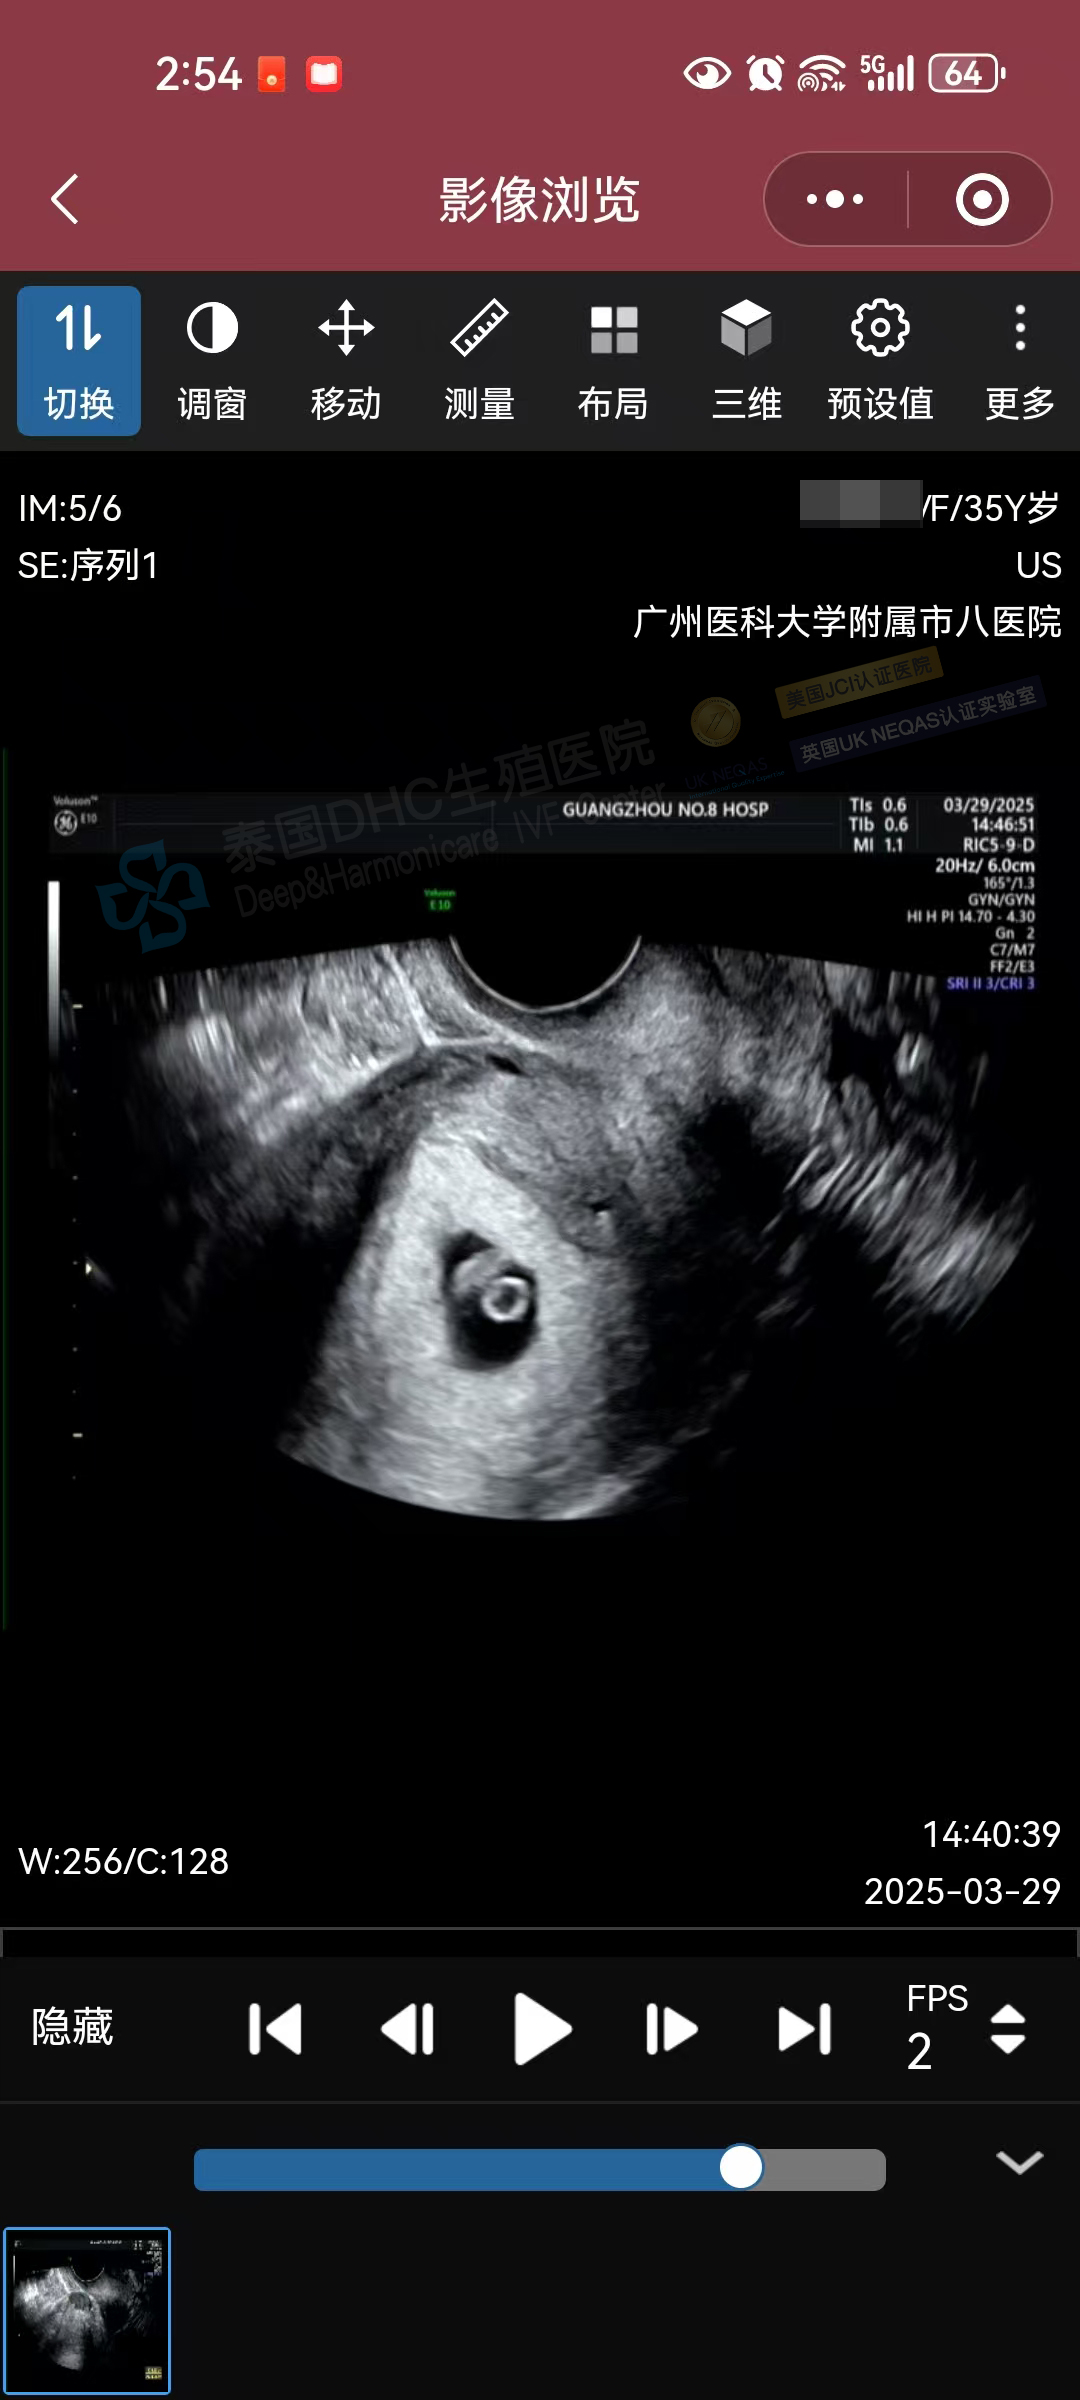

生命奇跡,如期而至!DHC三代試管助孕的35歲準(zhǔn)媽媽今日復(fù)查B超,再次迎來喜悅——小小寶貝胎心有力跳動,宣告著新生命的茁壯成長!?